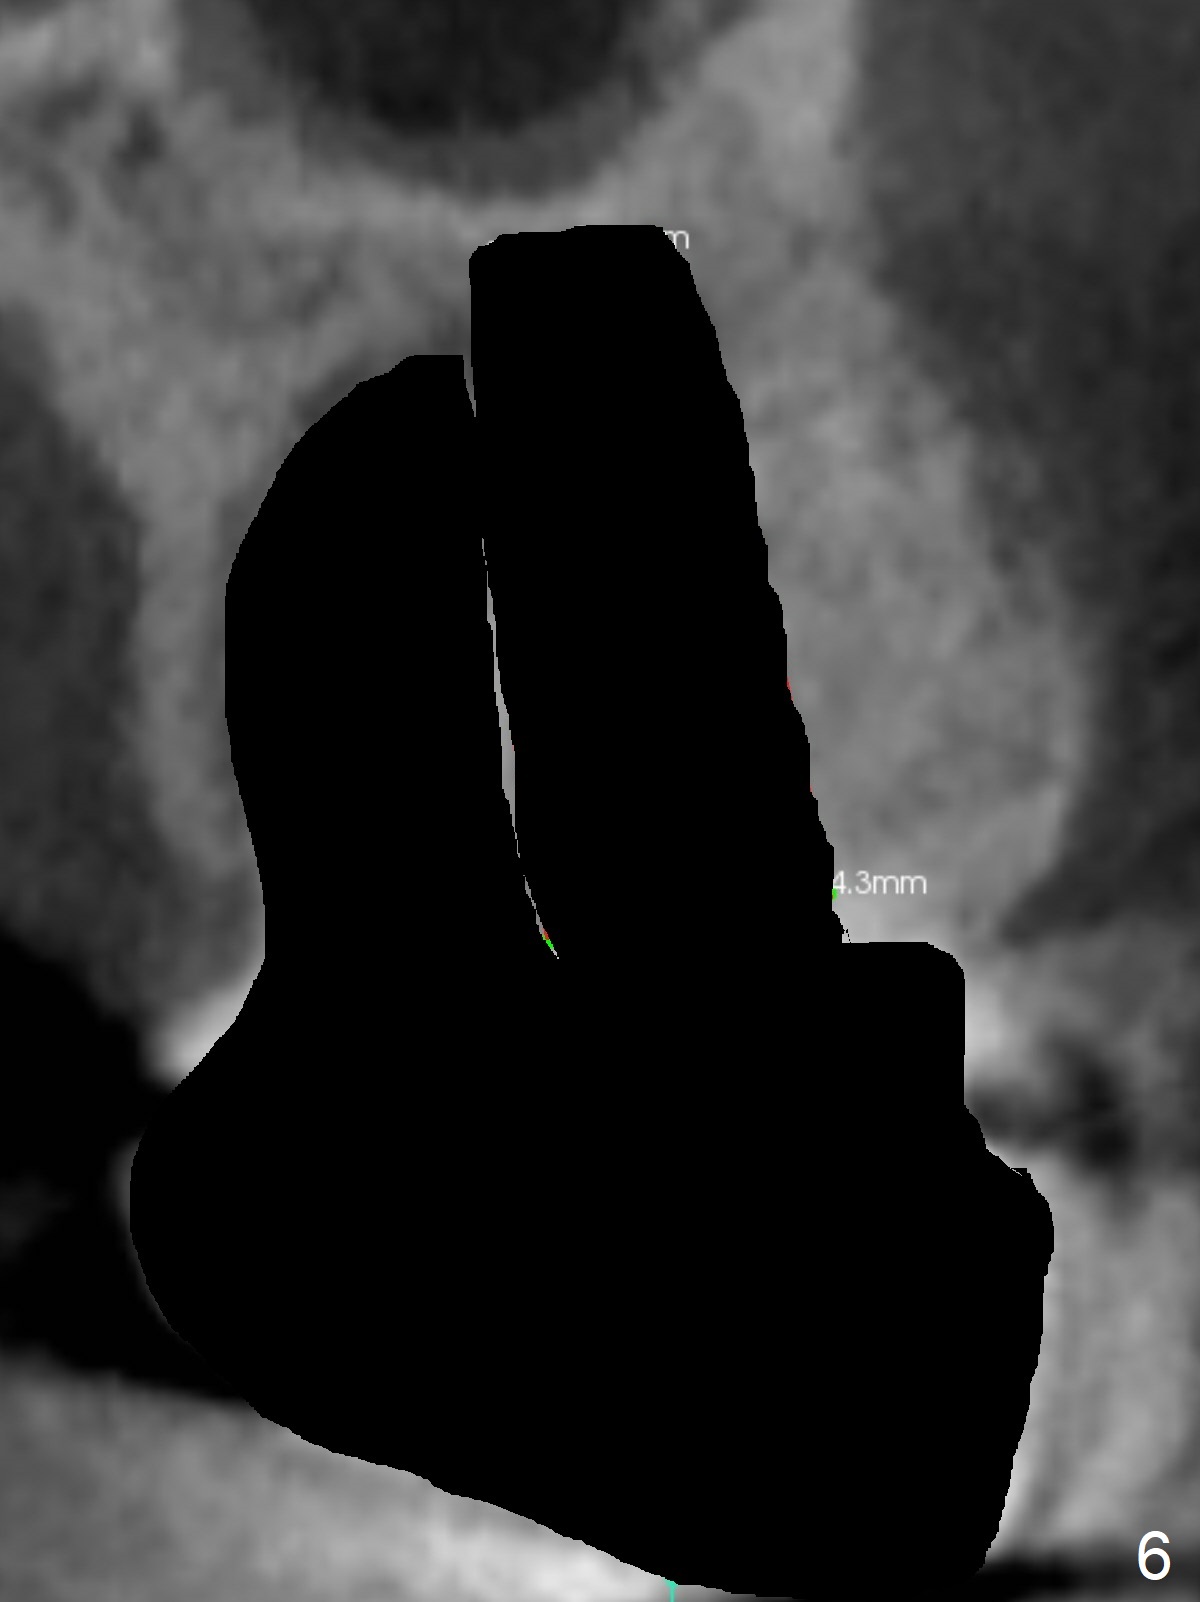

A 53-year-old man cannot chew on the left side with distal abscess in spite of RCT for #14 (* in Fig.1,2 (taken 11 ad 21 months postop, respectively)). After extraction (Fig.3 (CBCT coronal section) black area), start osteotomy with 2 mm drill (red outline) in the septum buccal to the palatal (P) socket). Following 2 mm drill removal (Fig.4), use 4.3 mm Magic Drill (red outline) for ~ 9 mm. When the osteotomy is being done, the osteotomy most likely shifts palatal (Fig.5 arrow) because of thin bone palatally. When the MD is removed (Fig.6), use Magic Sinus Lifter (Fig.7 pink) for sinus lift (arrow). The implant is to be 5x11 mm or larger. Because of the distal defect (Fig.1,2), start osteotomy mesially. Take Alginate impression before surgery for possible orthodontic treatment. Since bone density is high, use higher voltage and longer time for X-ray.